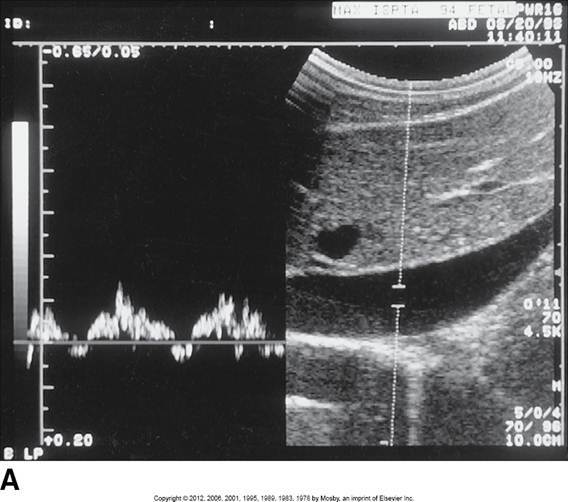

SMA